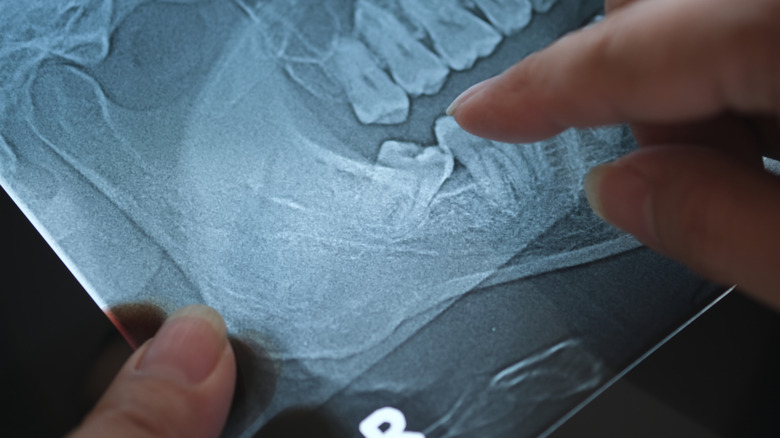

Because wisdom teeth typically erupt by the time the jaw has already grown to nearly full size, the other adult teeth have already settled into place. Without enough room to spare, impaction can occur, in which wisdom teeth push into the bottom of other molars. It's a painful experience that can increase the risk of infection. The only cure for impaction problems is wisdom tooth removal surgery.

But even if wisdom teeth do erupt successfully, they can still cause problems. The introduction of new molars so late in the body's development often pushes on the other teeth, causing overcrowding. Overcrowded teeth can be uncomfortable and increase the risk of infections and tooth decay. Until tooth regeneration becomes a reality, such tooth decay will still require fillings. The increased tightness between overcrowded teeth makes flossing difficult, and the subsequent misalignment can also create areas that are hard to reach with a toothbrush. While many people live with their wisdom teeth intact, dentists usually recommend removing them early on before they can cause problems. Wisdom teeth are one vestigial organ that we're better off without.